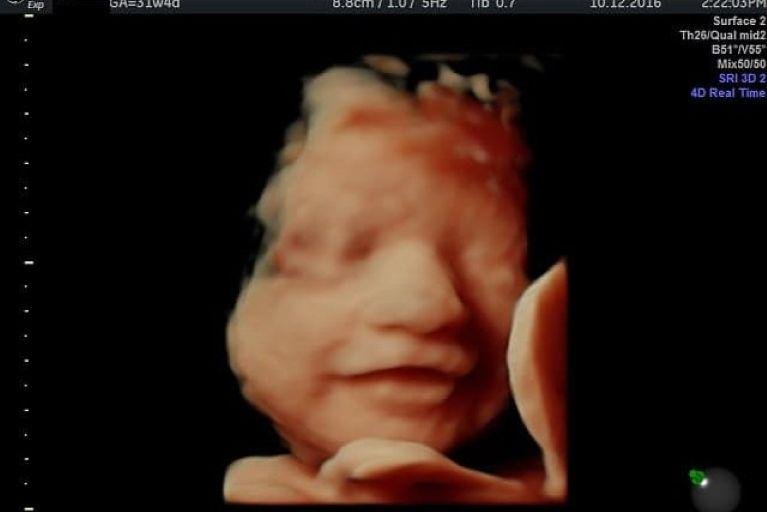

• Ultrassom Obstétrico

Acompanhamento completo da gestação com exames de alto e baixo risco, incluindo ultrassom obstétrico simples, com Doppler, Doppler com perfil biofísico fetal (PBF) e ultrassom morfológico do 1º, 2º e 3º trimestre.